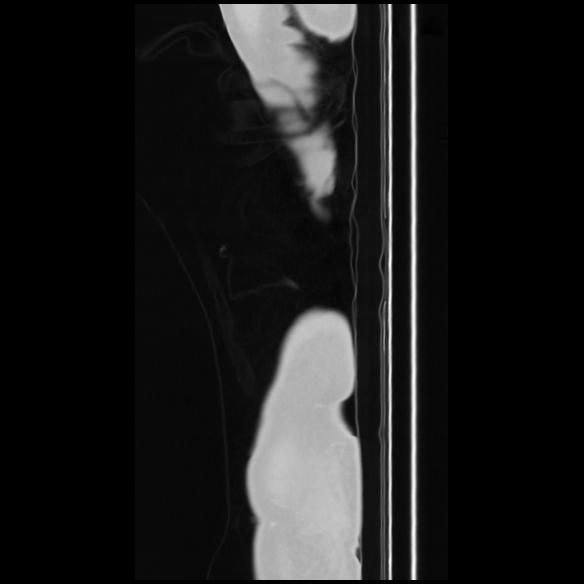

7 CUERPO,CE,Sagittal,3.000,CUERPO,Sagittal,